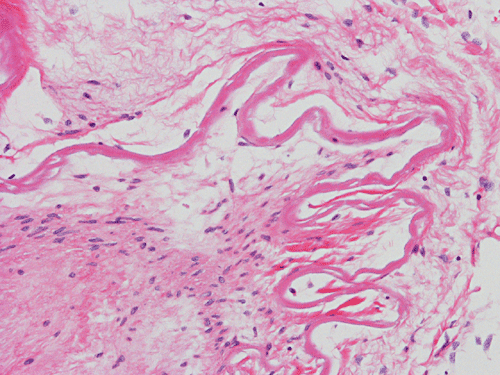

The followings are representative images from autopsy. Panel D to E are taken from the softened area. Panel G and H are taken from the blood vessels of the circle of Willis.